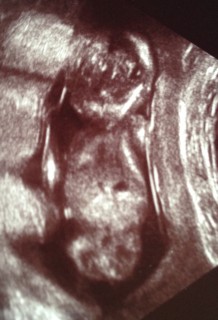

悪阻も治まりつつある中での検診。この日は寝てたのかあまり動いてはいませんでした。しかも背中を向けて、左手を耳の辺りに当てていて顔が見えませんでした(;_;)一緒に見ていた娘も顔が見えなかったので微妙な反応(笑)赤ちゃんの大きさは8.4cmで、順調でした。

BPD2.73cm

このあと4Dに切り替えてくれましたが

終始後ろ向きでした(>_<)

先生曰く、この時期のあかちゃんは大体後ろ向きだそうで、きっとまだ超音波に慣れてないからとの事でした!

次回の検診ではこっちを向いてくれる事が多いそう!楽しみ~